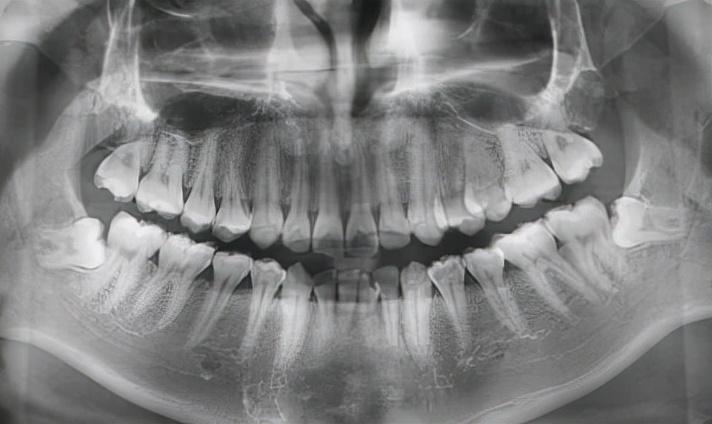

當然,還有其他更加奇奇怪怪的pose……

各類“不聽話的”下頜智齒

了解不同的拔牙情況之后,總的說來,其實就分四種(可對號入座)——

1、垂直生長、完全萌出的牙齒,單顆拔牙價格為 200~400 元左右;

2、沒有完全萌出,需要切開牙齦才能拔除的,價格在 300~500 左右;

3、完全生長在骨頭里面,需要使用微創(chuàng)方法拔牙的,價格在 800~1200 元左右;

4、極個別情況,如牙冠朝向相反方向生長等比較特殊的,價格為 1000~1500 元左右。